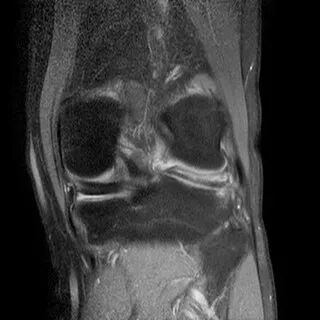

半月板斜行撕裂

最常见类型:斜行撕裂表现为:在矢状面上见III级高信号到达半月板关节面的上缘或下缘